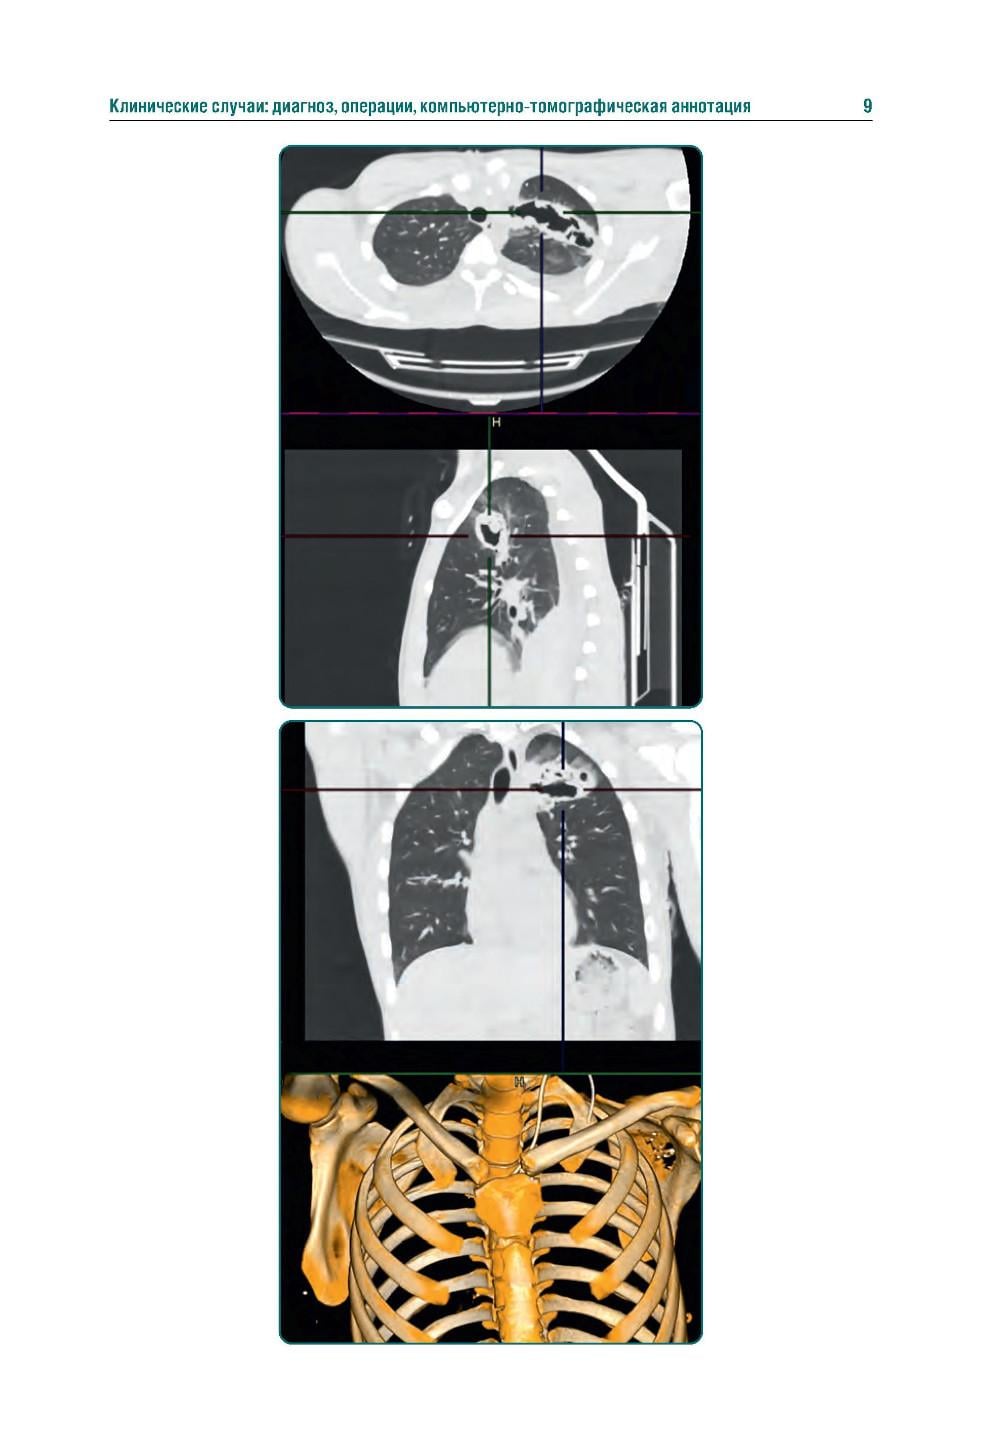

Издание представляет собой первый в Российской Федерации атлас, иллюстрирующий различные виды поражения легких, плевры и других структур грудной клетки у пациентов с боевыми ранениями. В современных условиях количество таких пациентов увеличивается, поэтому существенно возрастает значимость различных видов боевых травм, в том числе повреждений грудной клетки. В атласе представлены уникальные КТ-изображения различных видов боевой травмы грудной клетки, полученных в условиях современных вооруженных конфликтов. Помимо описания характера, условий получения травмы и выявленных повреждений, есть возможность просмотра изображений в формате DICOM. Атлас предназначен для врачей-рентгенологов, торакальных хирургов, пульмонологов, а также врачей других специальностей, занимающихся диагностикой и лечением пациентов с боевыми травмами.| Издательство | ГЭОТАР-Медиа |